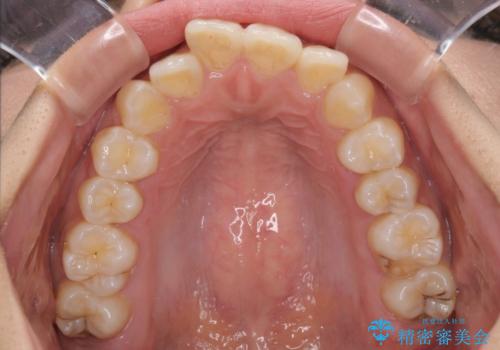

前歯のデコボコと隠れてしまう下顎前歯 インビザラインですっきりと改善

- 前歯のデコボコと、深い咬み合わせにより前歯が隠れていることを気にして来院された患者様です。

海外に長期滞在する予定があるとのことで、インビザラインにて矯正治療を行うこととしました。

インビザライン発注後に長期滞在先から2年間ほど帰国することができず、インビザラインの有効期限内に終了できるのか不安でしたが、矯正治療開始後は十分な装着時間を達成され、1年未満の期間で無事に終えることができました。